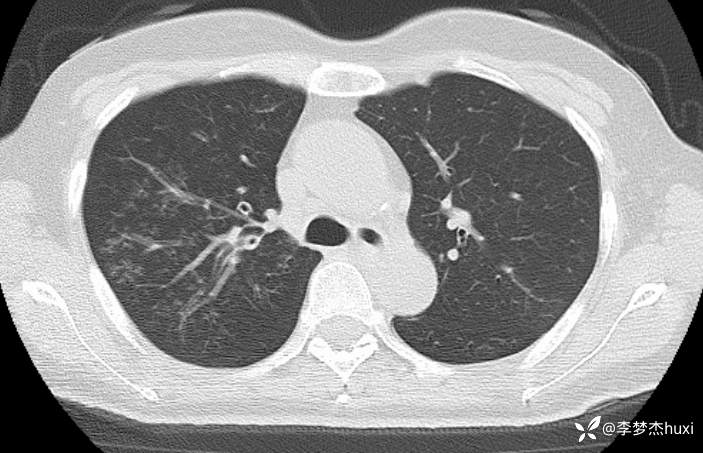

女性53岁,腮腺癌术后反复咳嗽、咳痰,胸部CT以树芽征为特点改变,最可能的是哪种疾病

【现病史及既往史】: 1.患者中年 女,患者于入院前5天无明显诱因出现咳嗽,咳痰,为黄绿色痰,量少,不易咳出,伴发热,最高体温不详,伴周身乏力,无胸痛,无呼吸困难,无恶心、呕吐,无腹痛、腹泻,无抽搐及意识障碍,院外未诊治,症状无好转,今患者及家属为进一步诊治前来我院就诊,门诊查胸部CT:右肺上叶占位性病变应考虑,右肺上叶空洞;右肺下叶占位?双肺炎症,支气管炎?右肺门淋巴结增大,双肺实性结节,纵隔结节,主动脉及冠状动脉钙化,右侧乳腺结节?建议结合超声,建议结合临床复查。门诊以“肺炎”收入院 。

2.既往高血压病史20余年,最高达180/?mmHg,目前口服“缬沙坦胶囊、硝苯地平控释片、酒石酸美托洛尔”等药物治疗,血压未监测;2008年因右侧腮腺腺样囊性癌于天津肿瘤医院行手术治疗,术后给予放化疗,2019年肿瘤原位复发,于北京大学口腔医院再次行手术治疗,2023-8发现肿瘤侵犯右耳道,目前口服仑伐替尼治疗约12个月;2023-11开始应用帕博利珠单抗注射液免疫治疗,患者右肺上叶占位,2024-7于沧州市中心医院行穿刺活检,病理:腺样囊性癌,2024-08于北京市某医院行“肺部射频消融术”;患者术后时常呛咳,否认“冠心病、糖尿病”病史,否认“肝炎”、“结核”等传染病史;否认外伤史,无输血史;否认食物、药物过敏史,预防接种史不详,系统回顾无特殊。。